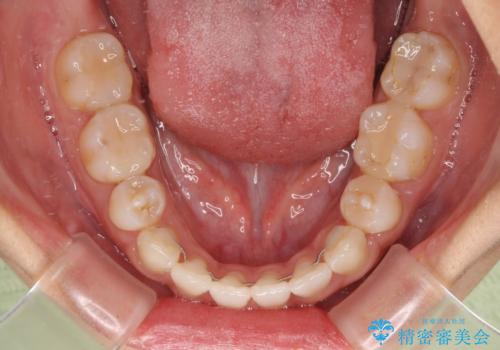

裏側装置での矯正治療は、上顎前歯の正中のズレをまっすぐに改善することが難しいのですが、きれいに整えることができました。

補助装置を用いて抜歯したスペースを速やかに閉じたことで、短期間での治療となりました。